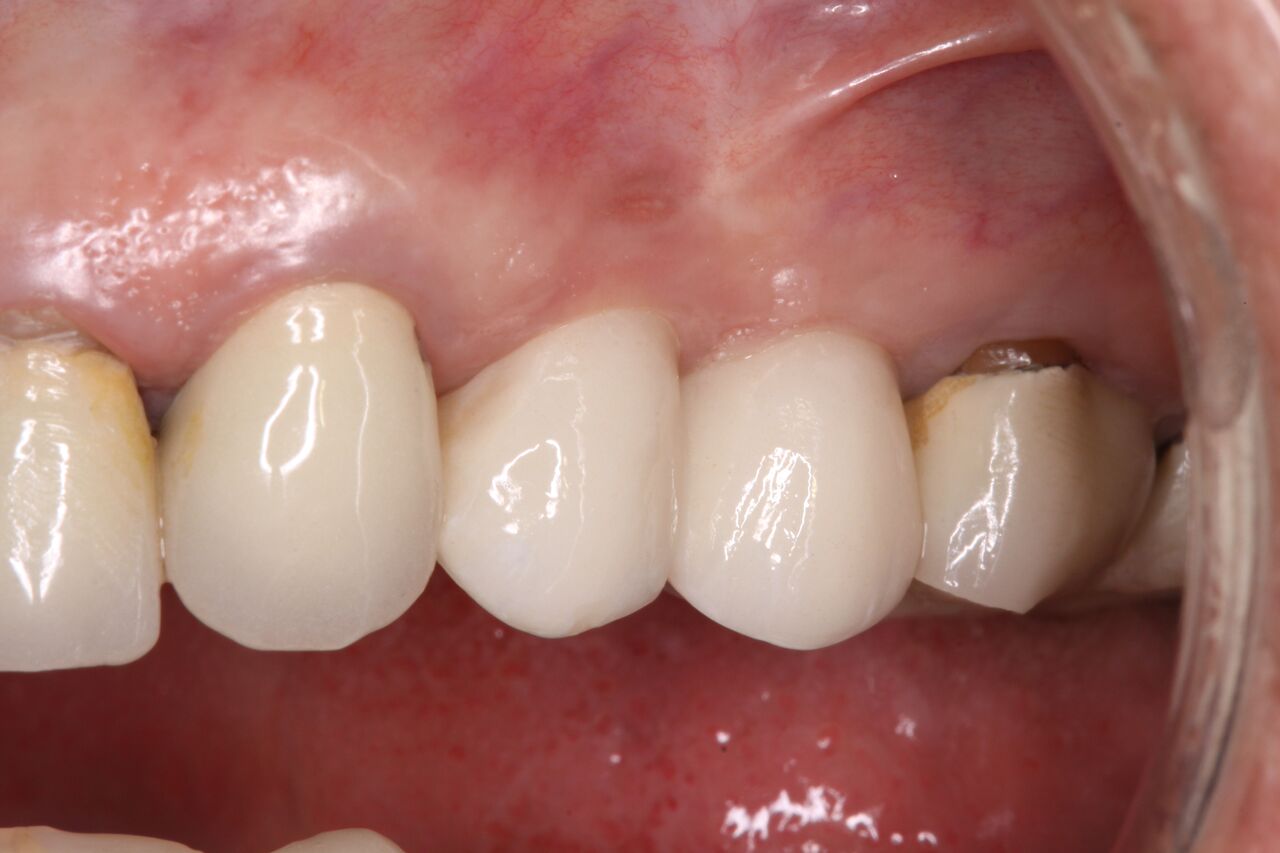

(15.) Clinical view of final individual crowns on Nos. 12 and 13.

Figure 15

(16.) Radiograph of final restorations on Nos. 12 and 13. Notice platform shift in No. 12 restoration.

Figure 16

The patient was prescribed antibiotics and analgesics and instructed in postoperative care particular to immediately provisionally restored implants. At 6 months, integration was confirmed (Figure 14) and the patient returned to her dentist for restoration. The implants were restored with individual cement-retained crowns with a platform shift for No. 12 restoration from the 6-mm diameter of the implant to a 5-mm diameter of the final restoration (Figure 15 and Figure 16).